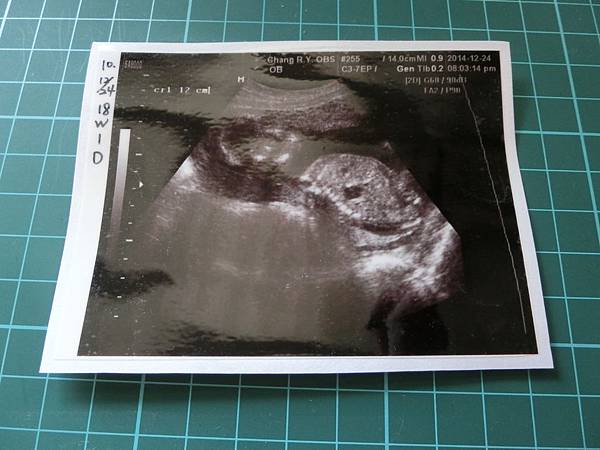

▼貼完就會像下面的超音波照片這樣,會有一層護膜

▼這樣就大功告成拉~是不是很EASY押

▼完成囉~~Lemon花了一個上午完成了17張寶寶的超音波貼膜